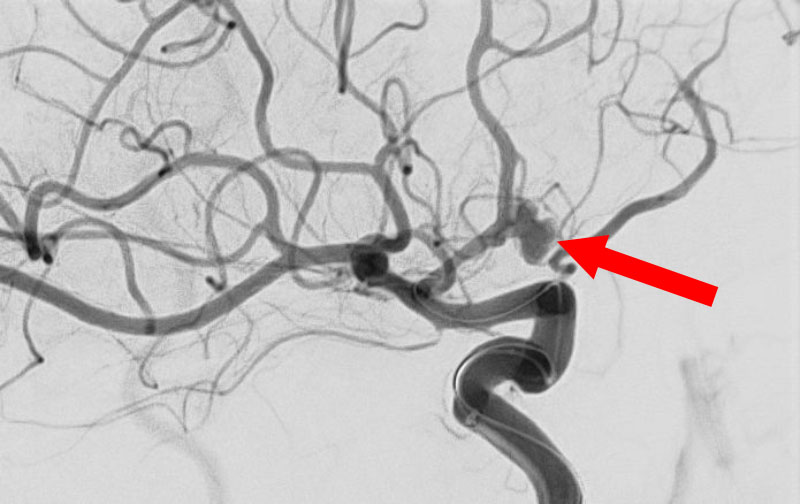

'25年11月

左内頚動脈脳動脈瘤

60代

大阪府の病院

No.1595 手術前

No.1595 手術中

No.1595 手術後